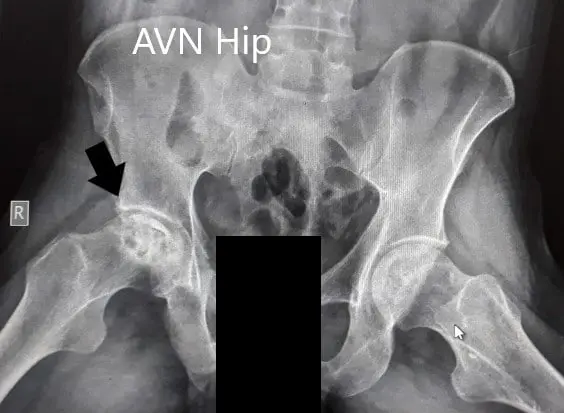

Imaging was acquired in the form of X-Rays which suggested the collapse of the femoral head on the right side. There was a loss of sphericity of the right hip with sclerosis and subchondral cysts. The left hip had an intact contour. MRI was advised of the pelvis with both hips.

Preoperative X-Ray of the pelvis with both hips in anteroposterior and frog-legged lateral views